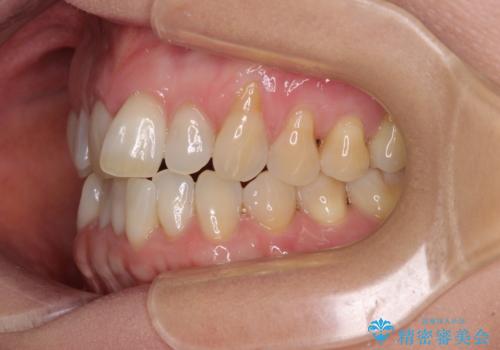

- 前歯の上下スペースによる食べにくさを気にして来院された患者様です。

インビザラインにより上下の前歯の隙間を閉じていくこととしました。

舌の突出癖があると上下前歯にスペースが開くため、矯正治療を機会に舌癖を改善するトレーニングを行ってもらい、矯正治療後の後戻りを防止するように指導しています。